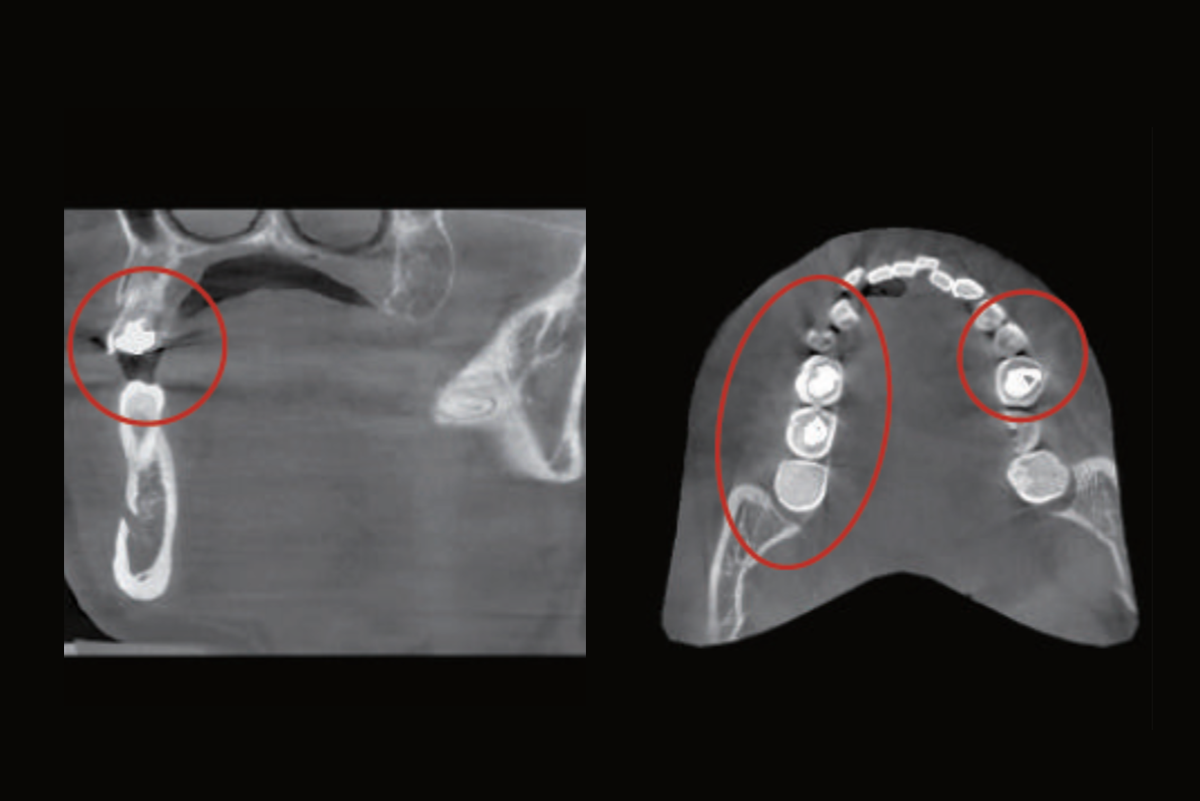

La Solution Smart MAR : système de réduction automatisé des artefacts lors de la prise de clichés